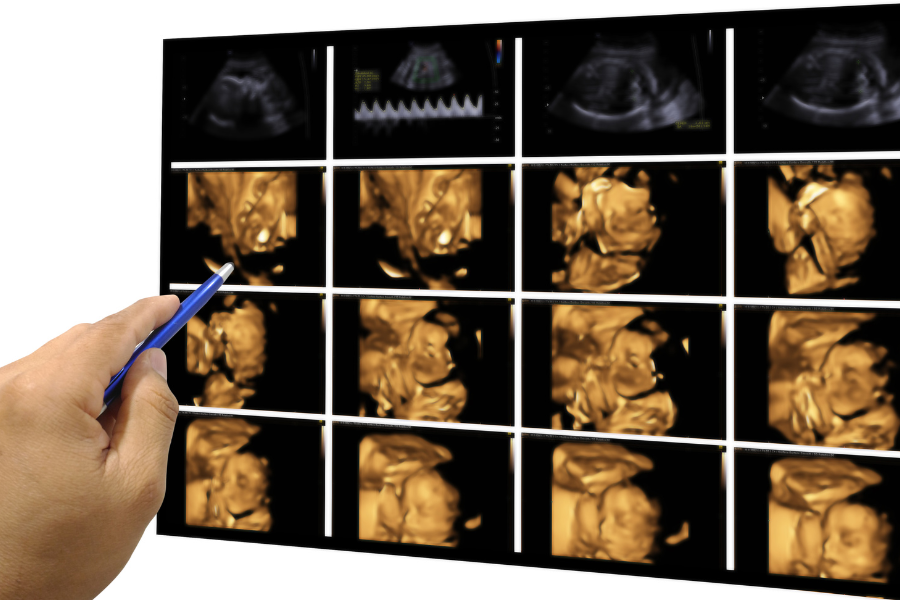

Album Photos pour Vos Bébés

Gardez un souvenir unique de votre grossesse avec un album photo de votre bébé. Lors des échographies, nous vous offrons des images de haute qualité de votre bébé, capturant des moments précieux pour vous et votre famille.

Album Photos pour Vos Bébés

Gardez un souvenir unique de votre grossesse avec un album photo de votre bébé. Lors des échographies, nous vous offrons des images de haute qualité de votre bébé, capturant des moments précieux pour vous et votre famille.

Album Photos pour Vos Bébés

Gardez un souvenir unique de votre grossesse avec un album photo de votre bébé. Lors des échographies, nous vous offrons des images de haute qualité de votre bébé, capturant des moments précieux pour vous et votre famille.